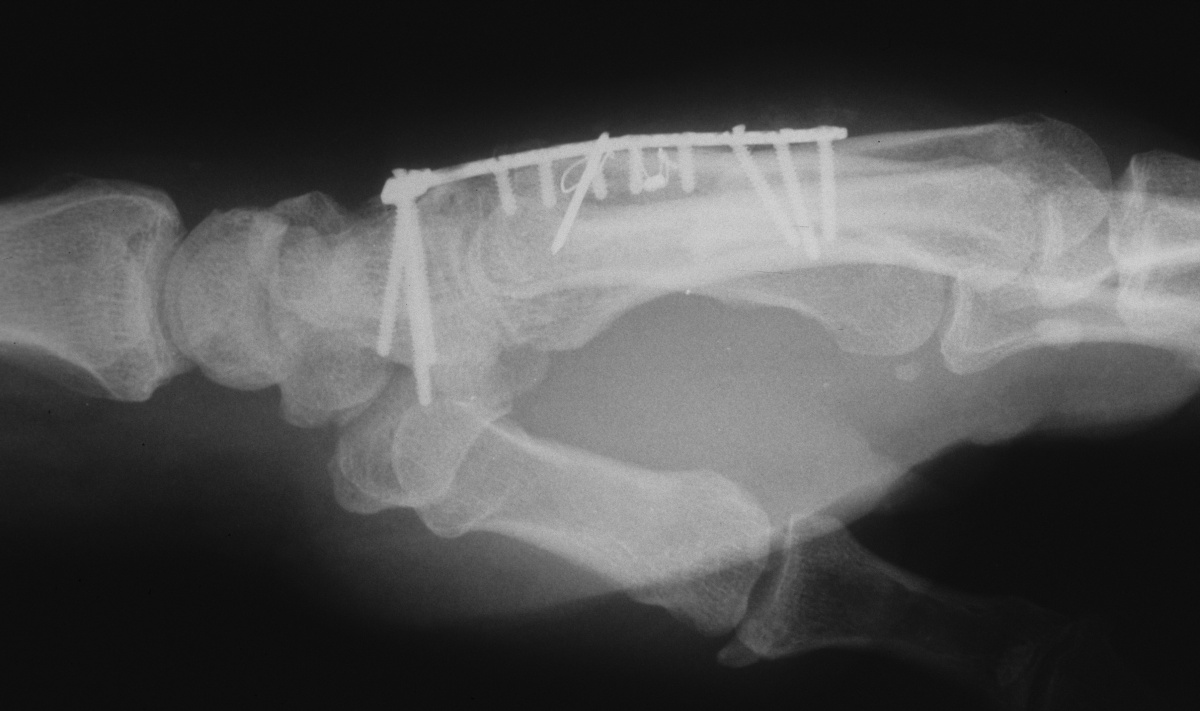

| Fixation of

bicortical iliac crest graft incorporating

carpometacarpal arthrodesis. |